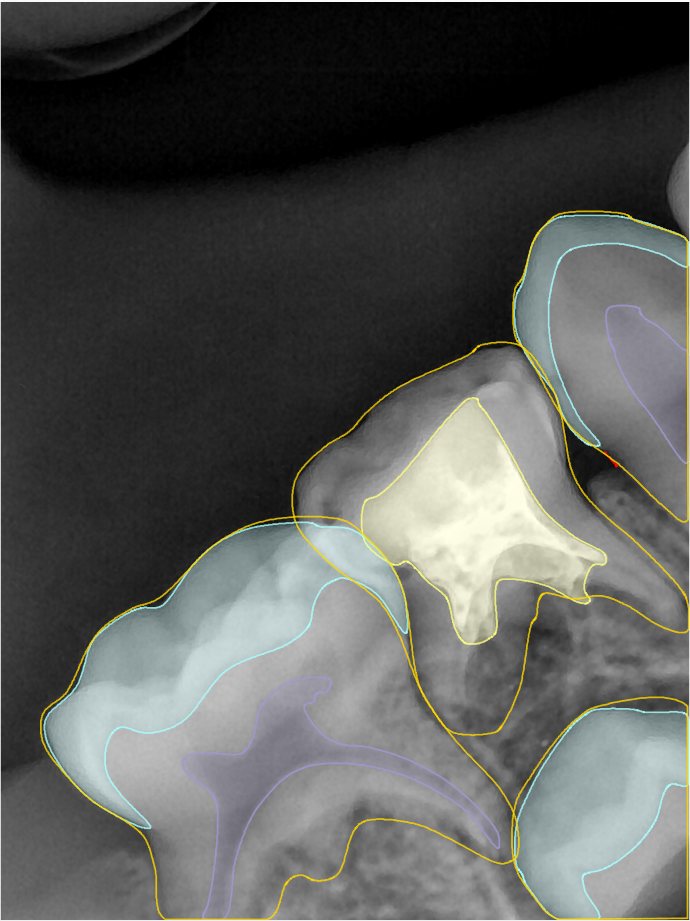

CR/DR 牙齿分割阶段记录

当前进展

- 完成了 CR/DR 牙齿相关分割训练

- 当前结果已经达到阶段预期,但仍有细节问题需要继续处理

相关测试

遇到的问题

- 训练过程中出现过 mask 下移问题

- 部分结果会出现 box 填充异常

- mask 边缘仍然有比较明显的锯齿感